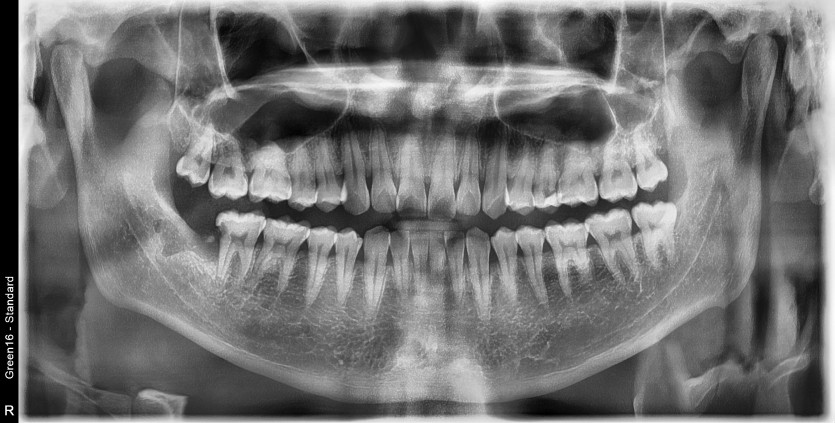

#48 사랑니 발치

구강 외과 전문의가 당일 발치했습니다.